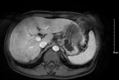

Hình 5. Kết quả chụp MRI gan-mật sau TACE lần 3 một tháng, khối u gan hai bên vẫn tăng sinh mạch nhiều, có nốt mới cạnh khối cũ, huyết khối nhánh phải tĩnh mạch cửa |

| | AFP: 1432ng/mL AFP-L3: 43% Pivka-II: 6023mAU/mL |

Bảng 2. Đánh giá đáp ứng điều trị sau TACE lần 3 chất chỉ điểm u tiếp tục tăng